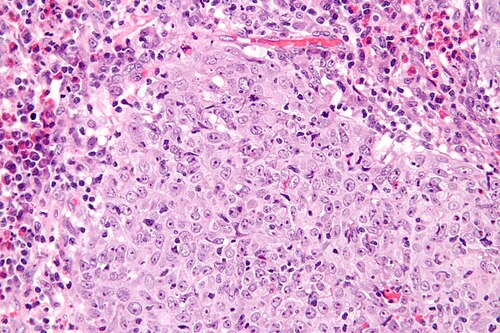

Clinical history

58 year old woman, cervical mass.

High magnification. H&E stain.